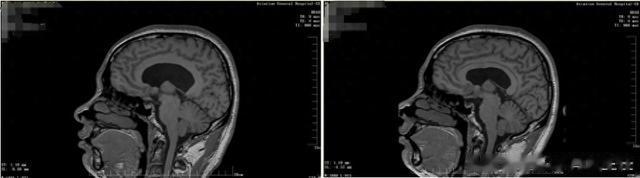

软性神经内镜术前术后对比

术后转归

患者小蔡的头痛症状术后即明显缓解,抑郁情绪及消化道症状逐步改善。复查显示造瘘口通畅,脑室系统明显缩小,恢复生理性流通。出院时患者感慨:"终于摆脱了每天与止痛药为伴的日子,感觉自己重获新生。"